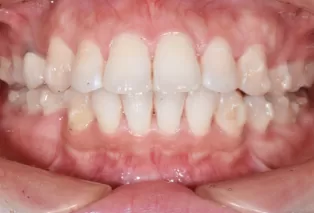

Photos intra-orales